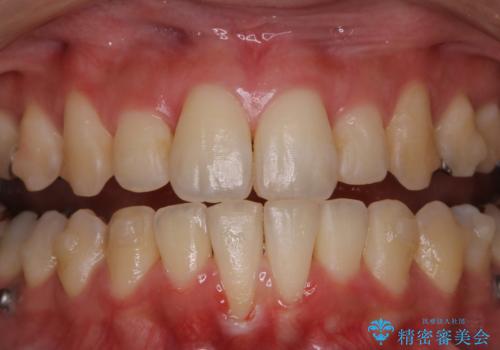

- 現在インビザラインでの矯正中で、歯の汚れが気になってきたためクリーニング希望とのことでした。PMTC60分コースを行いました。

毎日丁寧に歯磨きをしていても、日常生活での飲食物などにより着色してしまうことはあります。

PMTC(保険外治療)は、毎日の歯磨きで落としきれない汚れや、コーヒ、紅茶・タバコのヤニなどの着色も除去します。目には見えない歯と歯の間・歯肉の境目・インビザライン中はアタッチメント周囲などに残っているプラーク(歯垢)もしっかり取り除きます。PMTCでは専門的な機械や材料を使用して、徹底的に汚れを除去するため、虫歯・歯周病・口臭予防などにつながります。

また、仕上げのトリートメントでは歯の表面の凸凹にミネラルを補給して、ツルツルの表面に仕上げます。定期的にPMTCを行うことにより、歯質の強化になり着色がつきにくい状態になります。